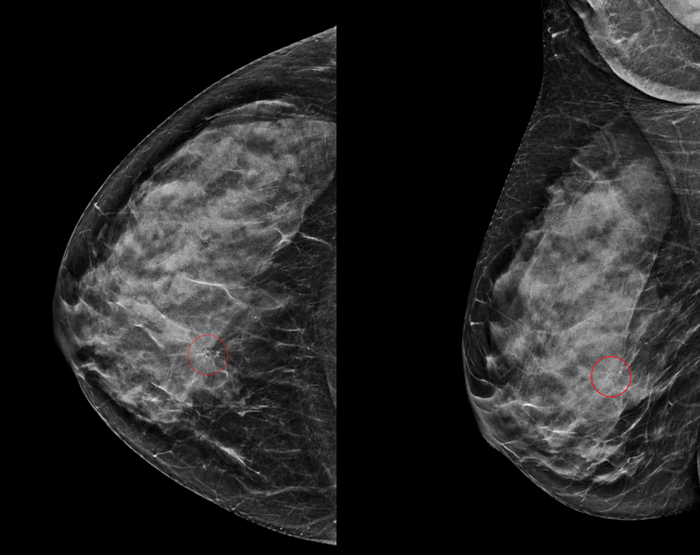

Анамнез: женщина 53-х лет, не имеющая в анамнезе личных или семейных заболеваний, при пальпации было обнаружено плотное и болезненное образование в медиальной части правой молочной железы, которое она впервые заметила примерно месяц назад. Образование постепенно увеличивалось в размерах и оставалось болезненным. Оно располагалось в нижне-внутреннем квадранте железы, в 10 см от соска, и при пальпации представляло собой поверхностное подкожное образование. Не было никаких изменений кожи, выделений из соска или системных симптомов. Результат УЗИ: При прицельном ультразвуковом исследовании было обнаружено овальное, ограниченное, параллелепипедное гипоэхогенное образование с небольшими кистозными участками и задним акустическим усилением. Образование размером 0,8 × 0,8 × 0,4 см располагалось в подкожной клетчатке, непосредственно под дермой, без видимой связи с кожей. Не было обнаружено внутренней васкуляризации, прилегающих воспалительных изменений, а также измененных внутригрудных или подмышечных лимфатических узлов. Результаты ММГ см. выше. Несмотря на доброкачественный вид, новообразование было классифицировано как BI-RADS 4 из-за появившейся боли, недавнего роста и отсутствия предыдущих исследований для сравнения. Была проведена тонкоигольная биопсия под контролем УЗИ, которая выявила пролиферацию веретенообразных клеток в пучках с участками Антони А и В. Иммуногистохимия показала диффузную экспрессию S-100 и Sox10, что подтвердило наличие доброкачественной шванномы.